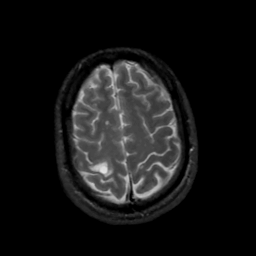

MR Study #5, March 10, 1991 -- Slice #42